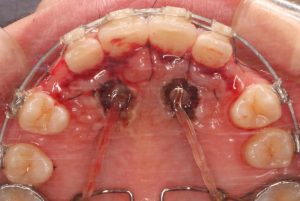

2を選択する代表的な症状は、埋伏歯を牽引するスペースが十分にあるか、矯正治療によってスペースを作ることが可能な場合です。下図は上顎両側の犬歯が上顎前歯部口蓋側に埋伏していますが、先ほどと異なり前歯の歯根吸収を引き起こしていません。乳犬歯も残存しており、犬歯を牽引して歯列に配列可能と判断しました。

埋伏歯を外科手術で開窓し、矯正装置を装着したところです。術直後で出血もあり見えにくいですが後方に牽引をしています。